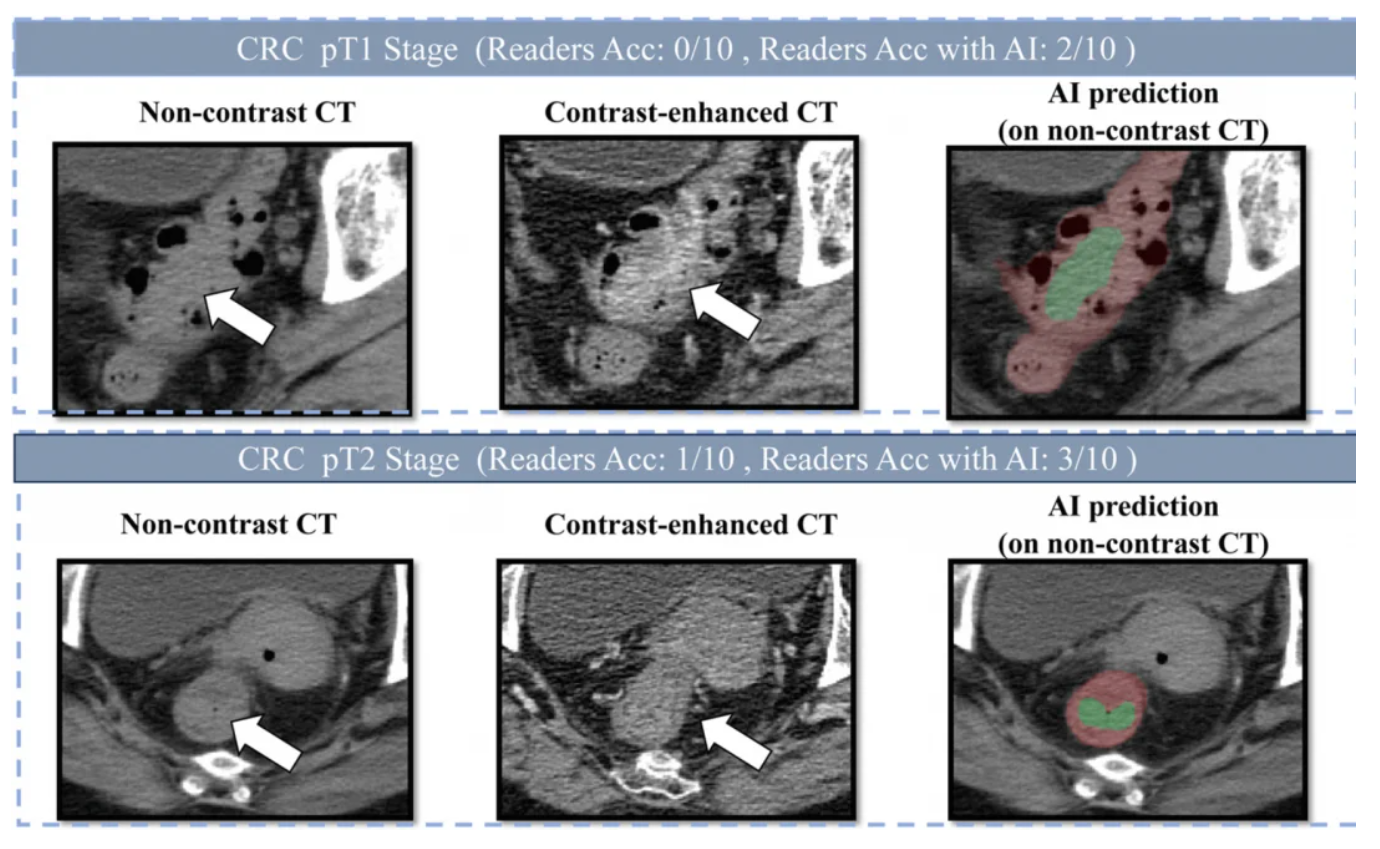

报告中展示的三组真实数据:

- 不漏诊(敏感性86.6%): 100个早期肠癌患者,它能抓出86个。

- 不冤枉人(特异性99.8%): 1000个没病的人,它只会错报2个,不会让你白挨一刀。

- 碾压人类医生: 在对比测试中,它的准确率比10位不同年资的放射科医生平均高出20.4%。如果有AI辅助,医生的看病水平还能再飙升14.5%。